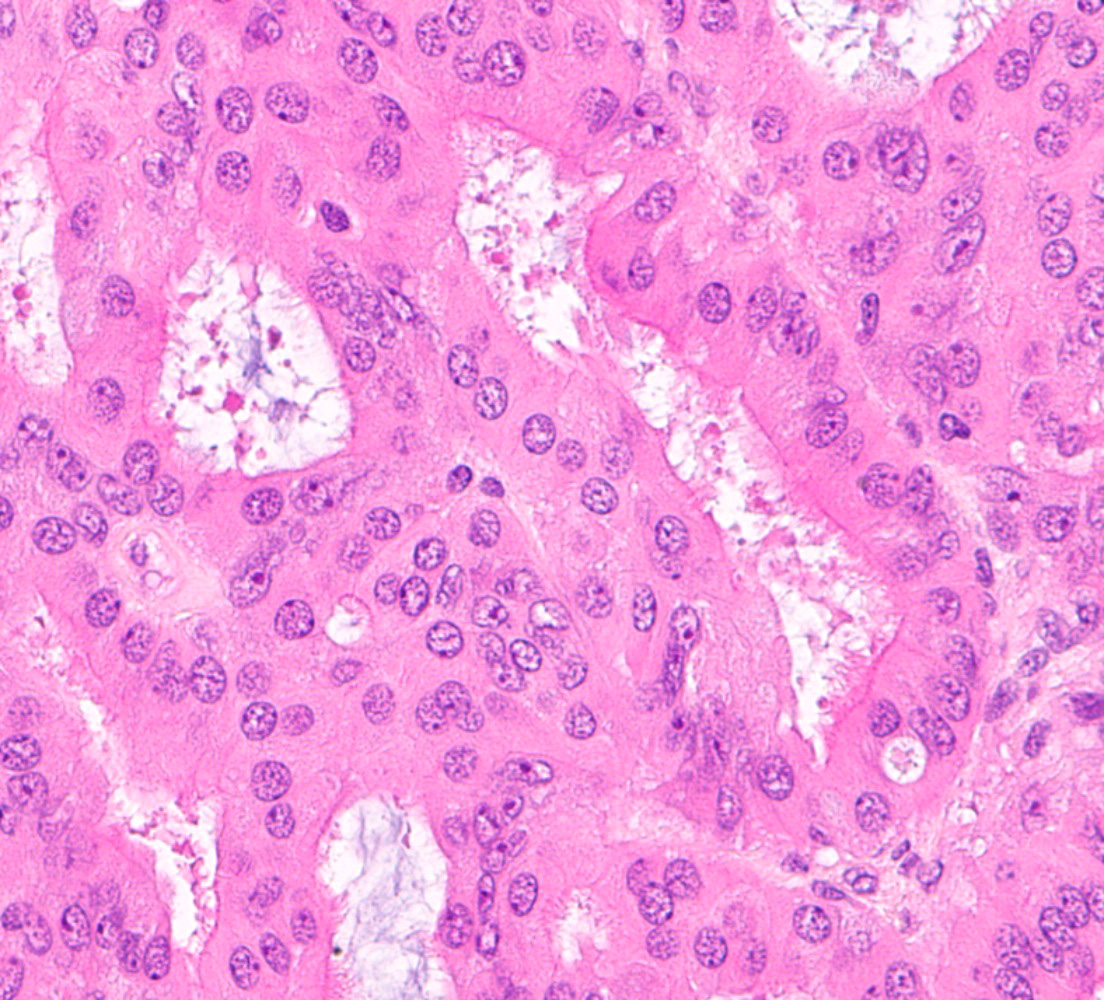

Microscopic (histologic) images

Contributed by Jessica L. Bentz, M.D.

- Squamous metaplasia:

- Subtypes:

- Morular (Gynecol Endocrinol 2020;36:460):

- Rounded to polygonal nests of immature squamous cells that fill the glandular lumen

- Rarely demonstrates keratinization, mitoses and central necrosis

- Generally cytologically bland but can obscure examination of the glandular architecture

- Morular borders are not well defined

- Characteristic intercellular bridges are not identified

- More commonly associated with endometrioid adenocarcinoma

- Squamous metaplasia:

- Intercellular bridges

- With or without histiocystic or giant cell reaction to the keratin